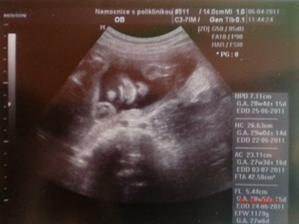

6.4.2011 - utz ve 30.tt - 29+5,odpovídáme 28+3 , odhad váhy 1180g ( prý to bude drobeček ) a je koncem pánevním ☹